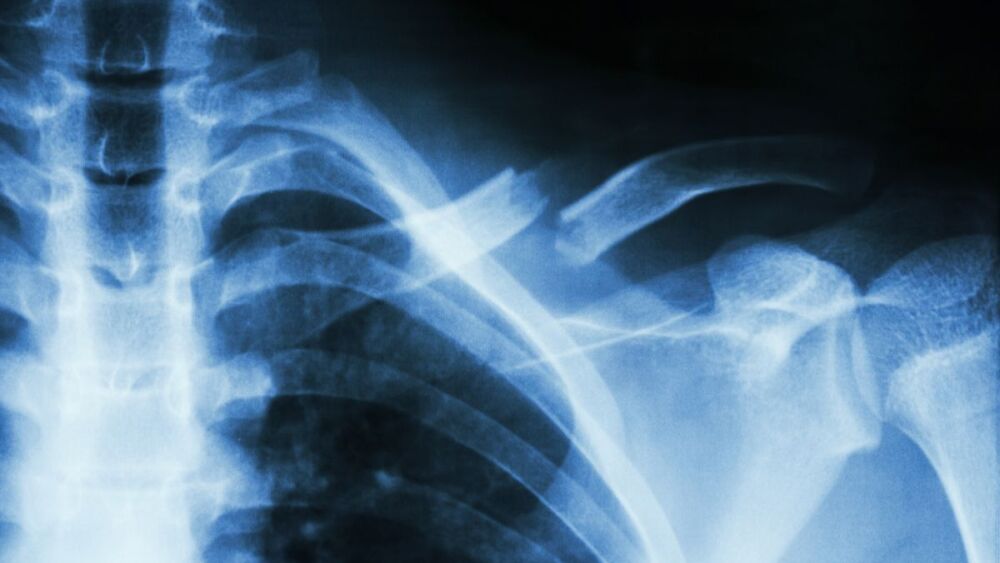

Treating broken bones and dislocations has been an important part of EMS as far back as EMS history goes. Early texts dedicated significant portions to applying splints, fashioning slings and tying swathes. Even today, initial EMT courses spend several hours using triangular bandages and board splints to immobilize extremity fractures.

Advances in technology and increased focus on the many medical maladies patients present with has not decreased the importance of managing musculoskeletal injuries. While many medical conditions may not worsen if treatment is put off until arrival at the hospital, the same cannot be said for fractures and dislocations. Without proper splinting and care prior to transport, injured patients may experience unnecessary pain, worsened soft tissue damage and permanent neurovascular deficit.

The secondary survey is based on the MOI, patient complaint and findings of the primary survey, and may include a complete head-to-toe physical assessment or a more focused examination. Uncover and visualize areas of concern for any obvious deformities, bruising or swelling that might be an indication of fractures or for soft tissue injuries such as abrasions and lacerations that could be a clue to underlying damage.